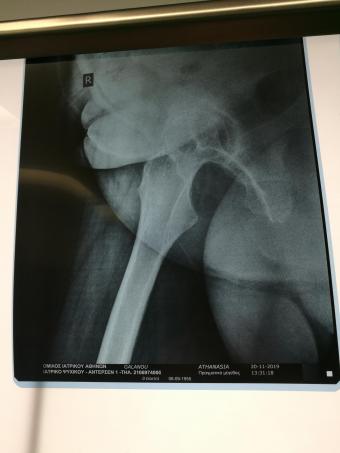

Компанія Lima надала стажування в ортопедичній приватній клініці місті Афіни Греція в листопаді 2019 року. Ендопротезування кульшового суглоба протезами компанії Lima малоінвазивним передньо-латеральний доступом у професора Христодулоса.